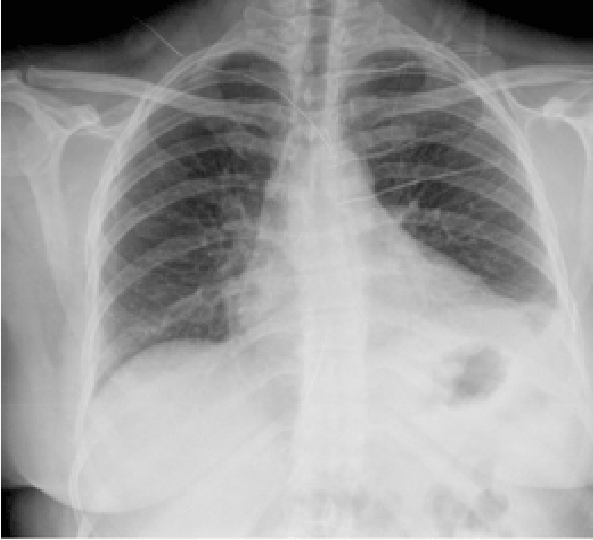

我们报告一例45岁无明显病史的女性患者,她接受腹腔镜Nissen's胃底折叠术治疗伴有胃食管反流的巨大食管裂孔疝。术后6个月,她出现持续性打嗝,打嗝的强度和频率影响了她的生活质量;使用PPIs和开始促动力学并进行诊断试验-钡转运试验、压力测定和pH测定-结果均正常。由于临床症状持续存在,也进行了腹部CT扫描和内窥镜检查,结果也正常。治疗方案中添加了巴考芬。症状持续存在,并在ch正常。进行了电生理学研究,观察到左侧膈神经的大小小于右侧膈神经。因此决定对左侧膈神经进行麻醉阻滞(图1)。首先用2%的利多卡因阻断神经,从而产生短暂的症状改善。因此,使用持续时间较长的麻醉剂左旋布比卡因进行第二次渗透,导致打嗝完全消失。一周后重复相同的程序-灌注左旋布比卡因24小时通过在超声和电刺激的帮助下放置神经周围导管。48小时后,打嗝再次出现,每小时发作一次,因此决定再重复灌注24小时,拔出导管后三天,患者无症状。观察到左半膈肌抬高由于左侧膈神经麻痹,在胸部X光片上进行了观察,但没有明显的呼吸反应(图2)。在上述操作两年后,患者仍然无症状。

图2:麻醉阻断膈神经后几个月的胸片